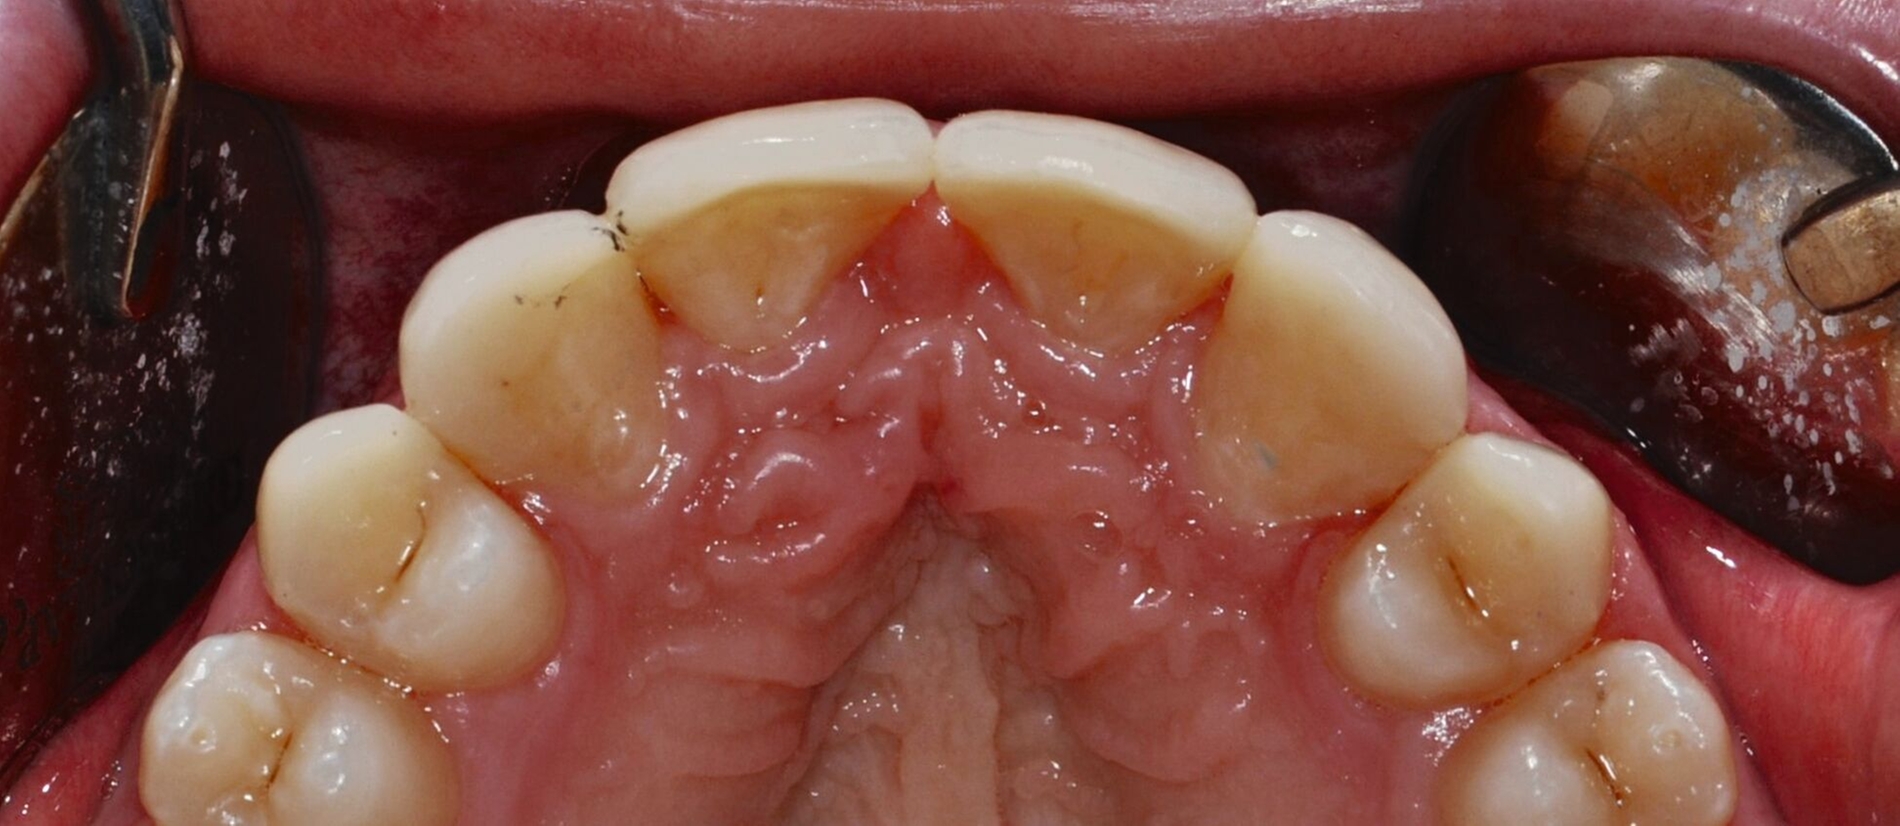

Nach einer präventiven Vorbehandlung in Form einer Professionellen Zahnreinigung und eines individuellen Mundhygienetrainings erfolgt die erste Behandlungssitzung, in der direkte Zahnformkorrekturen mit Komposit (IPS Empress Direct Dentin & Enamel A2, Ivoclar Vivadent, Liechtenstein) in Mehrfarben- und Mehrschichttechnik an den Zähnen 13 und 23 vorgenommen werden. Dabei werden die Eckzähne morphologisch zu seitlichen Schneidezähnen umgestaltet. Zur Orientierung der finalen Inzisalkantenlängen und ‑ausdehnungen dienen palatinal-inzisale Silikonstopps, die auf Basis des diagnostischen Wax-ups gefertigt wurden. Die Approximalflächen werden mithilfe einer individuellen Matrizenverschaltechnik unter Verwendung anatomisch vorgeformter Kunststoffmatrizen gestaltet. An den Zähnen 12 und 22 werden die vorhandenen mesialen Kompositrestaurationen entfernt, bevor Abformungen beider Kiefer mit Alginat erfolgen.

Anschließend werden laborgefertigte Non-prep-Kompositveneers aus dem gleichen Material für die Zähne 12 und 22 hergestellt. Diese werden in einer zweiten Sitzung nach dem Abstrahlen des Zahnschmelzes beziehungsweise der Restaurationsinnenflächen mit Al₂O₃-Pulver und dem Einbringen von Retraktionsfäden adhäsiv (IPS Empress Direct & Flow A2) eingesetzt. Zur Optimierung der Papillenästhetik wird der breite mediale Papillenbereich vor dem Einsetzen der Veneers durch eine externe Gingivektomie reduziert. Der marginale Gingivaverlauf der Zähne 12 und 22 wird unter Berücksichtigung der Lachlinie und in Absprache mit dem Patienten nicht nach apikal auf das Niveau der Eckzähne verlagert. Zusätzlich werden die Zähne 14 und 24 im Bereich der bukkalen Höckerspitzen direkt mit Komposit umgeformt und harmonisch an die neue Frontzahnsituation angepasst.

Die direkten und indirekten Kompositrestaurationen werden abschließend mit Skalpellen (Nr. 12), diamantierten Schallspitzen, rotierenden Instrumenten und Soflex-Scheiben ausgearbeitet, in statischer und dynamischer Okklusion kontrolliert, entsprechend eingeschliffen und auf Hochglanz poliert. Die Hygienefähigkeit der marginalen Bereiche wird sichergestellt und dem Patienten werden zur häuslichen Reinigung der Zahnzwischenräume passende Interdentalraumbürstchen angepasst (Abbildung 3).